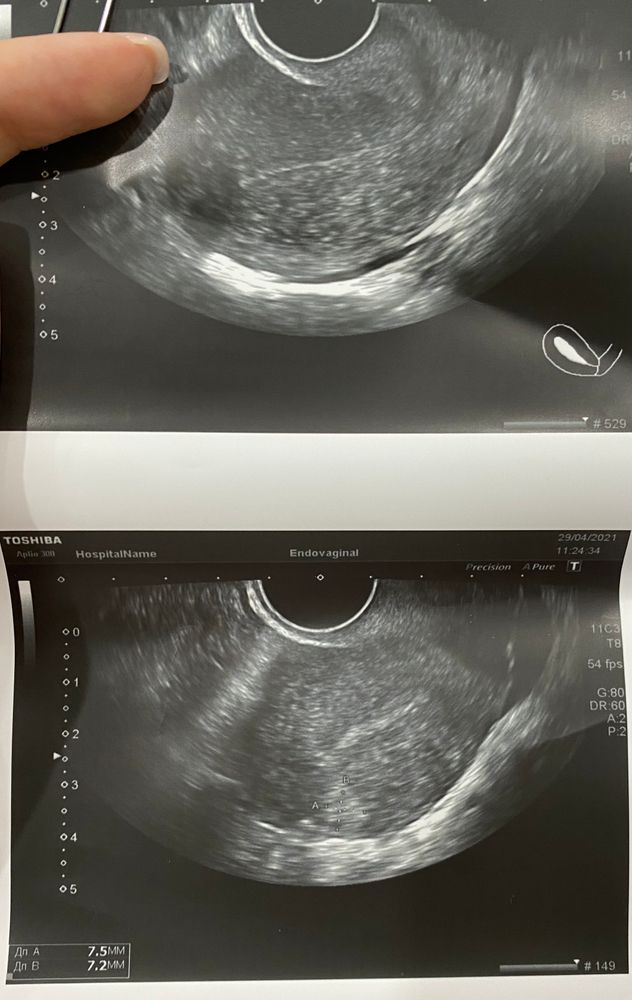

В прошлом цикле мне делали гистероскопию, убирали полип. Пошла я на узи после месячных и... что за участок повышенной эхогенности в эндометрии?

Узист сказала, что полипом назвать это не может пока с уверенностью, слишком все незначительно. Неужели опять полип растёт? Только же все убрали... К г попаду только после праздников.

Ко всему прочему на 8 д.ц. за маткой откуда-то взялась свободная жидкость, но тоже в очень маленьком количестве. Я в замешательстве... Откуда могла взяться?